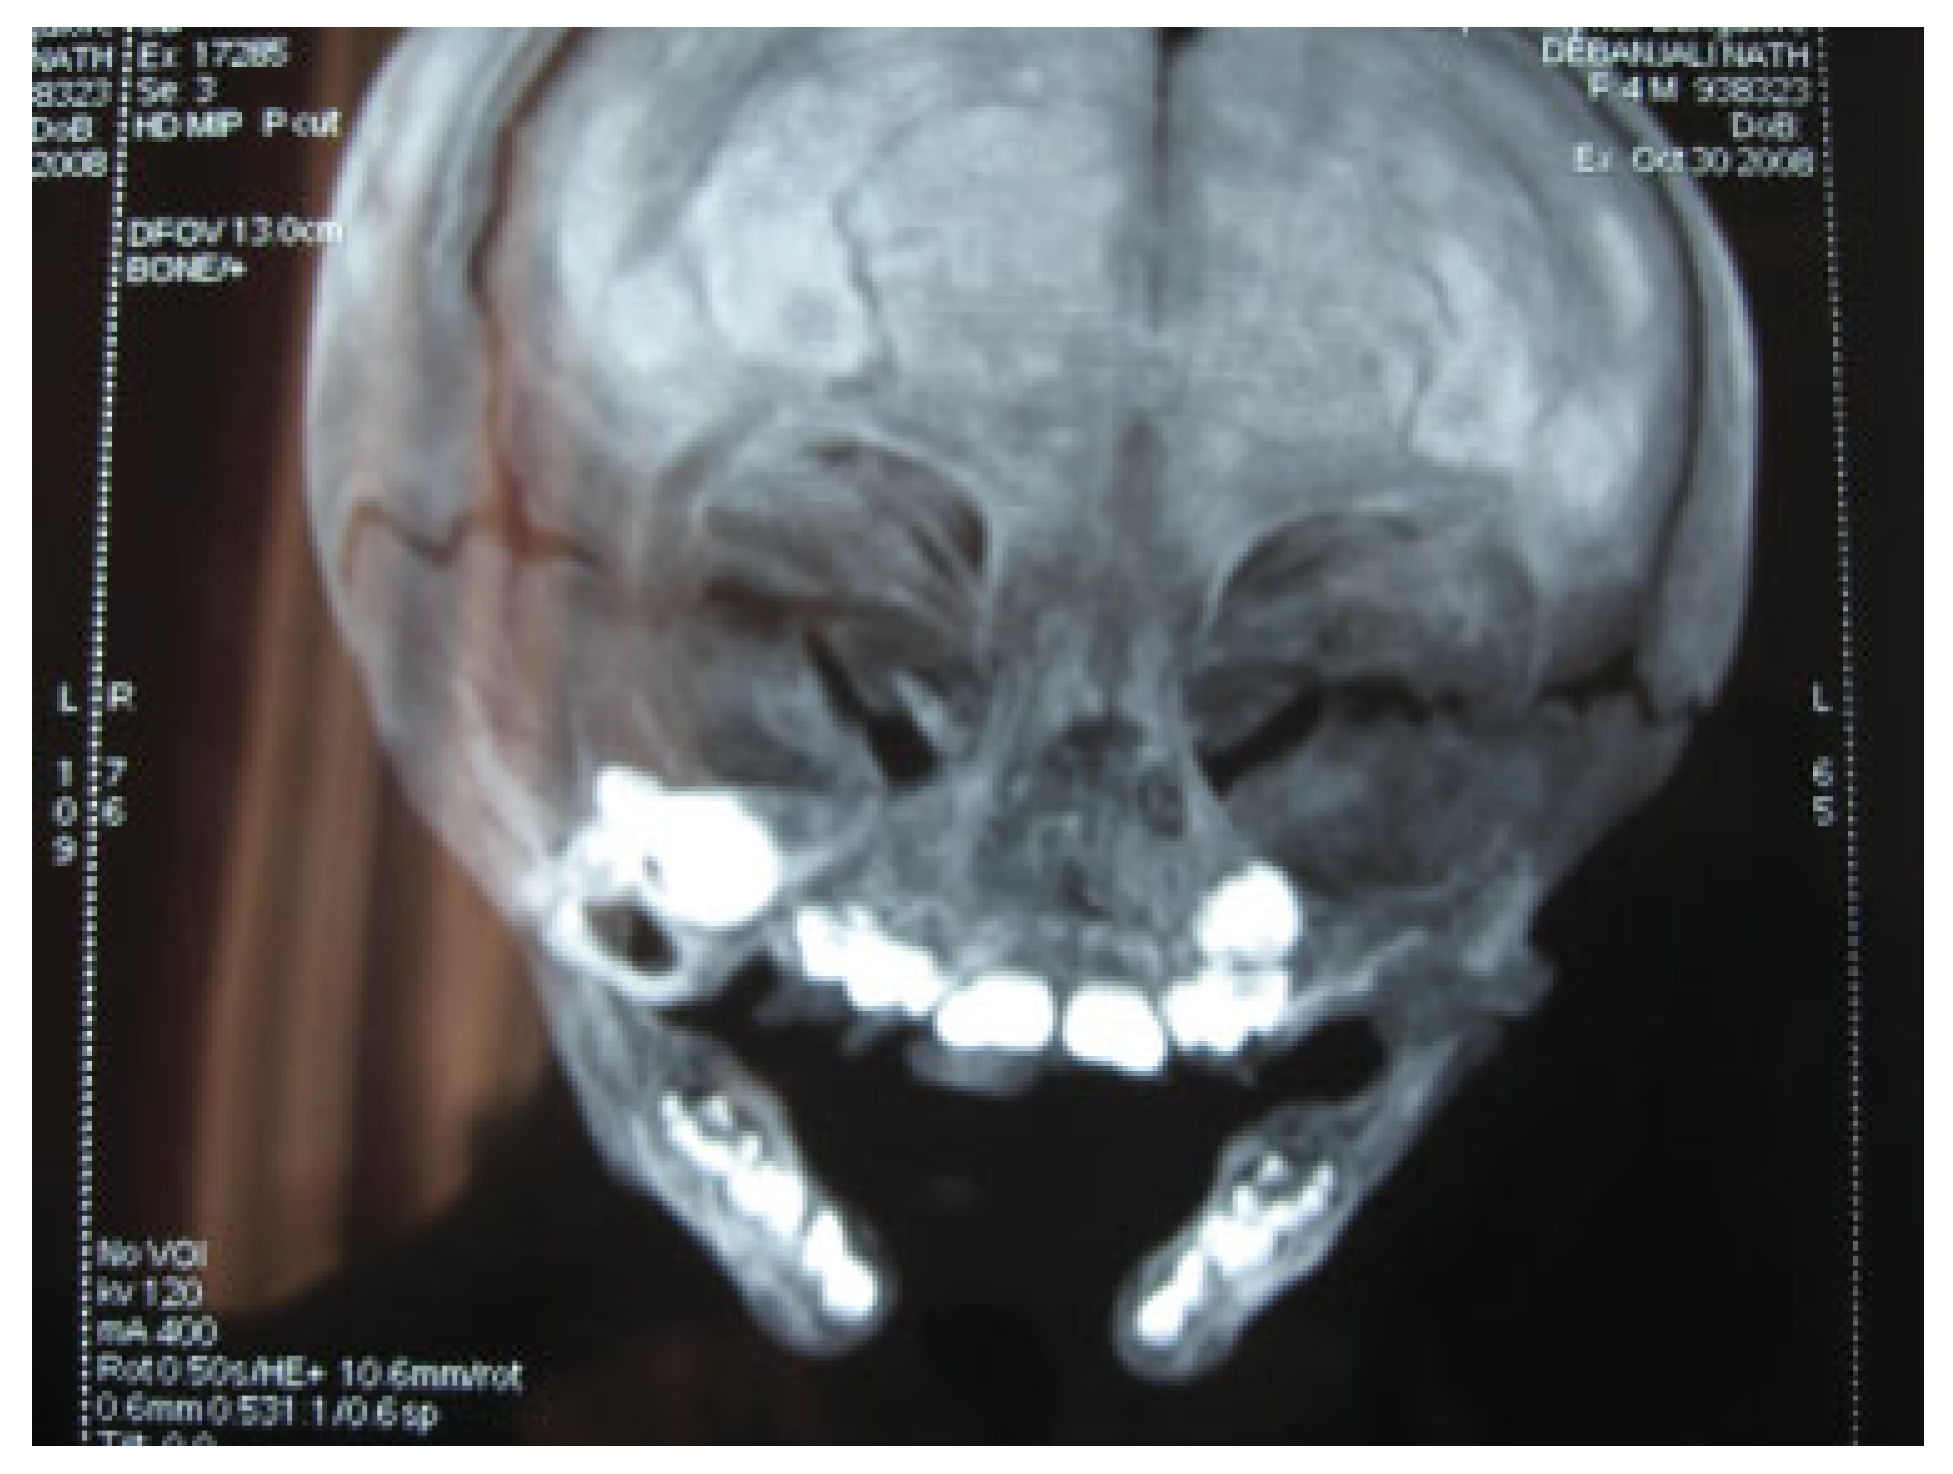

Complete Midline Cleft of Lower Lip, Mandible, Tongue, Floor of Mouth with Neck Contracture: A Case Report and Review of Literature

Case Report